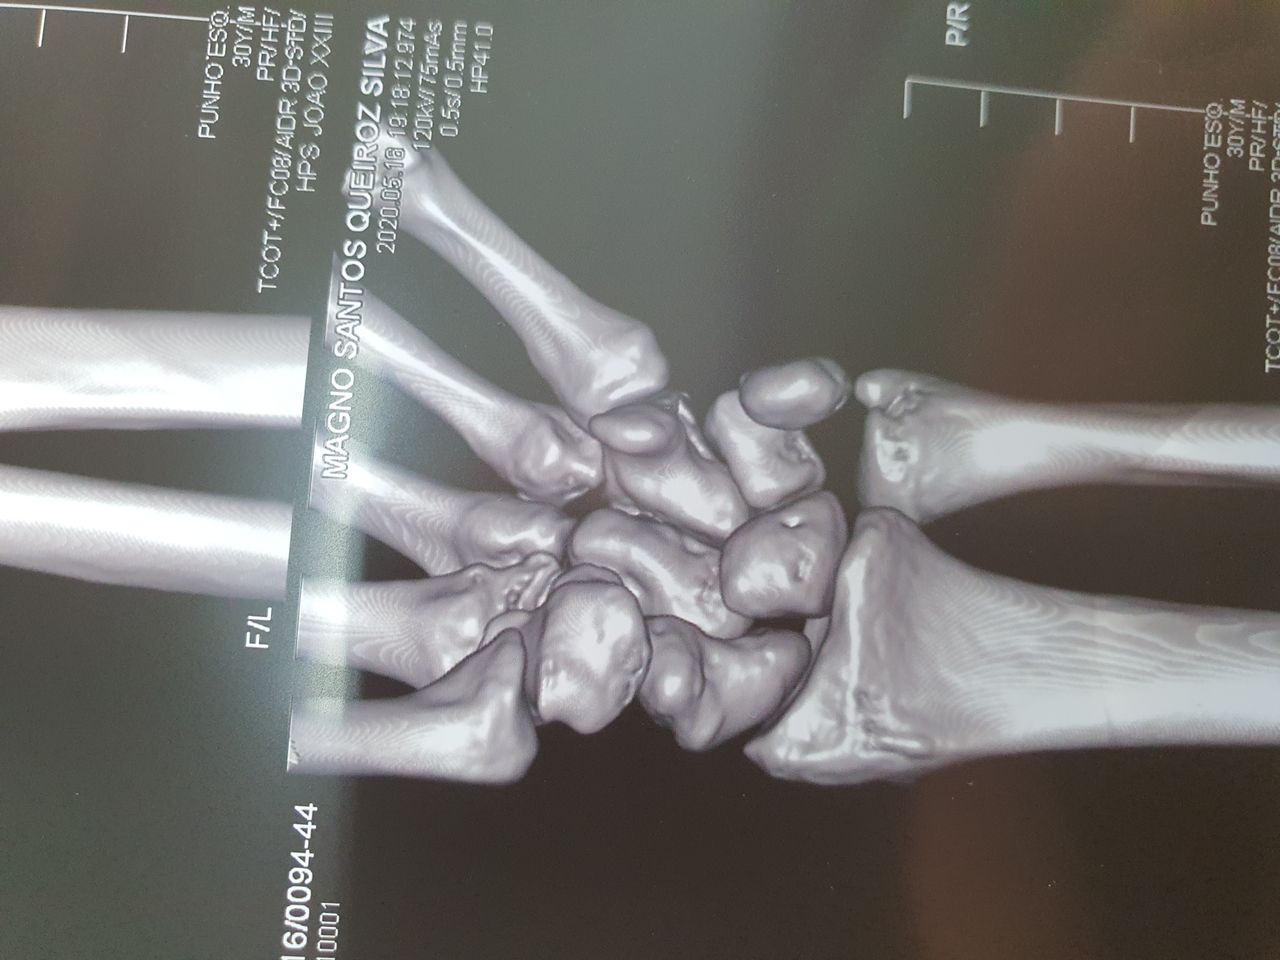

-ESCAFÓIDE: Tratamento da Fratura e da Pseudo-artrose do Escafóide com ou sem DISI e outras complicações, bem como Lesões Ligamentares da Mão e Punho, incluindo as do Ligamento Escafo-lunar do Carpo. Bennett, Rolando, Barton, Monteggia, Galleazzi e outras fraturas especiais ou comuns.